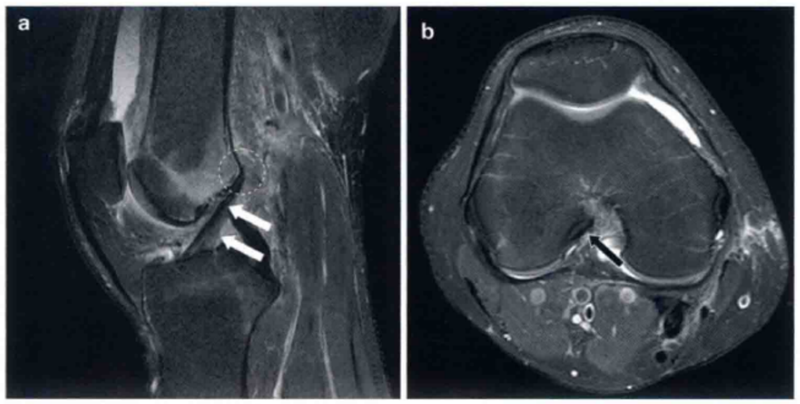

必须从膝关节MRI上ACL的信号强度和形态来对ACL进行评估。从矢状位片上可以显示ACL自股骨止点到胫骨止点的完整形态。横断面上可以显示其股骨止点情况,一般与矢状位片结合来分析(图1)。在矢状位片上,正常的ACL形态应沿着Blumensaat线与髁间窝的顶平行。正常情况下,ACL在T1和T2序列像上均是低信号,但其内部通常有一些混杂条纹信号,不能认为ACL有损伤。根据ACL在胫骨上的相对位置,其有2条纤维,即前内侧束(anteromedial bundle,AMB)和后外侧束(posterolateral bundle,PLB)。然而,在MRI上这两束纤维并不总是完全分开的。从水平位和冠状位片上也有可能看到分开的两束纤维。

图1 a和b分别显示的是在T2图像中矢状位和轴位正常的ACL。

a显示绷紧,可见明显的ACL低信号(白色箭头)。在a中也显示正常的胫骨附着点(圆形标记)。b显示在水平面上正常的股骨附着点